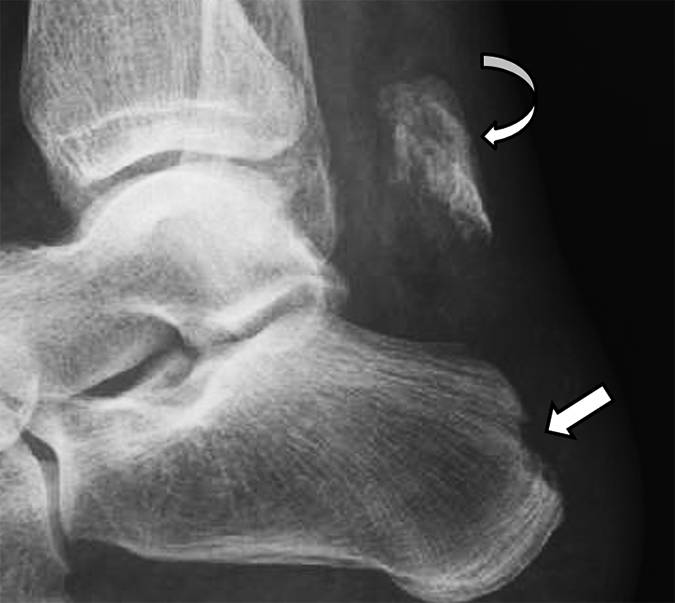

图3 -患者59岁,1型跟骨骨折,症状急性后足跟疼痛。 侧面放射照片显示优越位移的骨片(弯曲的箭头)和跟部结节的上部方面的供体位点缺陷(直箭头)。